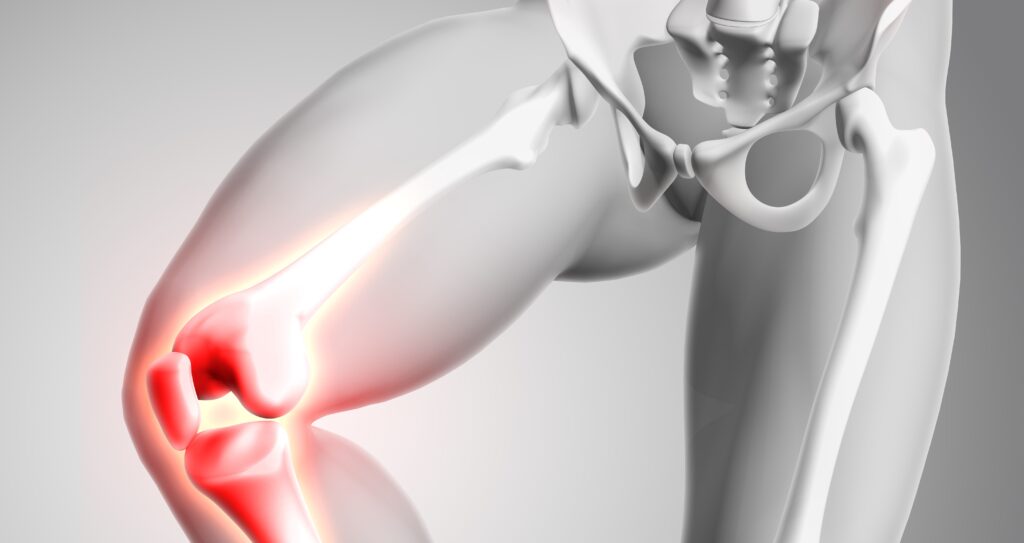

Joint disorders represent one of the leading causes of disability worldwide, affecting aging populations, athletes, and individuals with metabolic or inflammatory conditions. Osteoarthritis alone impacts more than 500 million people globally, placing a significant burden on healthcare systems and quality of life. In recent times, collagen supplements have emerged as an effective solution to maintain joint integrity, cartilage resilience, and connective tissue health.

The Lancet, in a review by Shoulders and Raines, emphasizes that Type II collagen is the primary structural component of articular cartilage, while Type I collagen provides tensile strength to tendons and ligaments. The degradation of these collagen networks is a hallmark of joint degeneration and inflammatory arthritis.

Chronic joint pain is strongly linked to low-grade inflammation and immune dysregulation. Collagen has been shown to modulate inflammatory pathways that contribute to joint discomfort.

2. Cartilage Regeneration and Repair

Joint stiffness is often caused by cartilage thinning, synovial inflammation, and connective tissue rigidity. Clinical trials consistently show improvements in mobility following collagen supplementation.